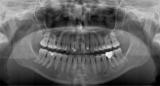

Radiografia Panorâmica (Fig. 1) fornece informações do Complexo Dento-Maxilo-Facial e a Radiografia específica (Fig. 2) da Articulação Temporandibular (Posições: Boca Aberta e Boca Fechada) temos a imagem das posições da movimentações do Côndilo

A Ortopantomografia (Radiografia panorâmica) fornece imagem do Complexo Dento-Maxilo-Faciai auxiliando o Cirurgião -Dentista [1,2,3,4].

A Radiografia sinaliza para as avaliações das Estruturas Ósseas (Fig. 1) e com detalhes da ATM (Articulação Temporomandibular (Fig. 2).